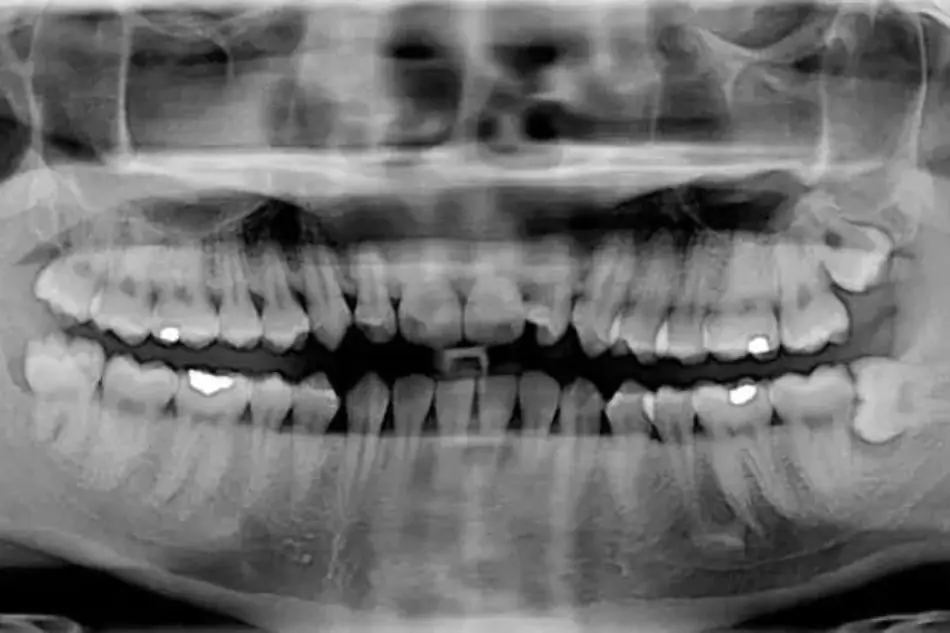

- ortopantomografia HD

- ortopantomografia CHILD